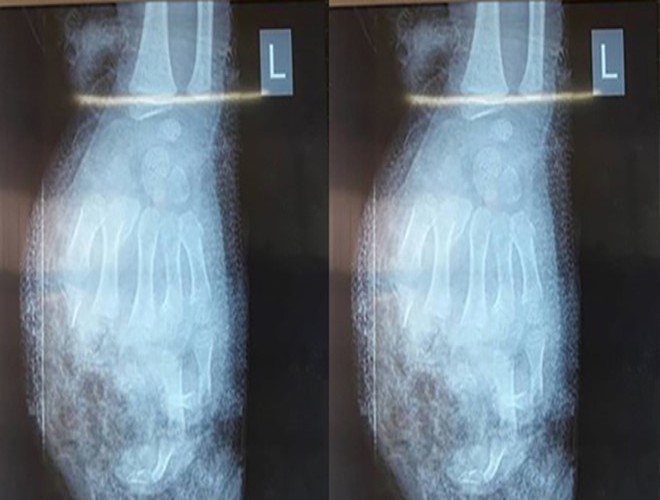

Bất ngờ tiếng nổ lớn phát ra, mọi người trong nhà phát hiện bàn tay của G bị nát bươm và đã nhanh chóng đưa em tới bệnh viện đa khoa của tỉnh. Bác sĩ điều trị cho G cho biết: bệnh nhân bị tổn thương nghiêm trọng, không còn khả năng nối lại các ngón tay

Bác sĩ Bệnh viện Sản nhi Nghệ An xác định tay trái H bị dập nát, phải cắt 3 ngón, tay phải chấn thương nặng. Ngoài ra, vụ nổ còn khiến bệnh nhân H tổn thương ở mắt, suy giảm thị lực